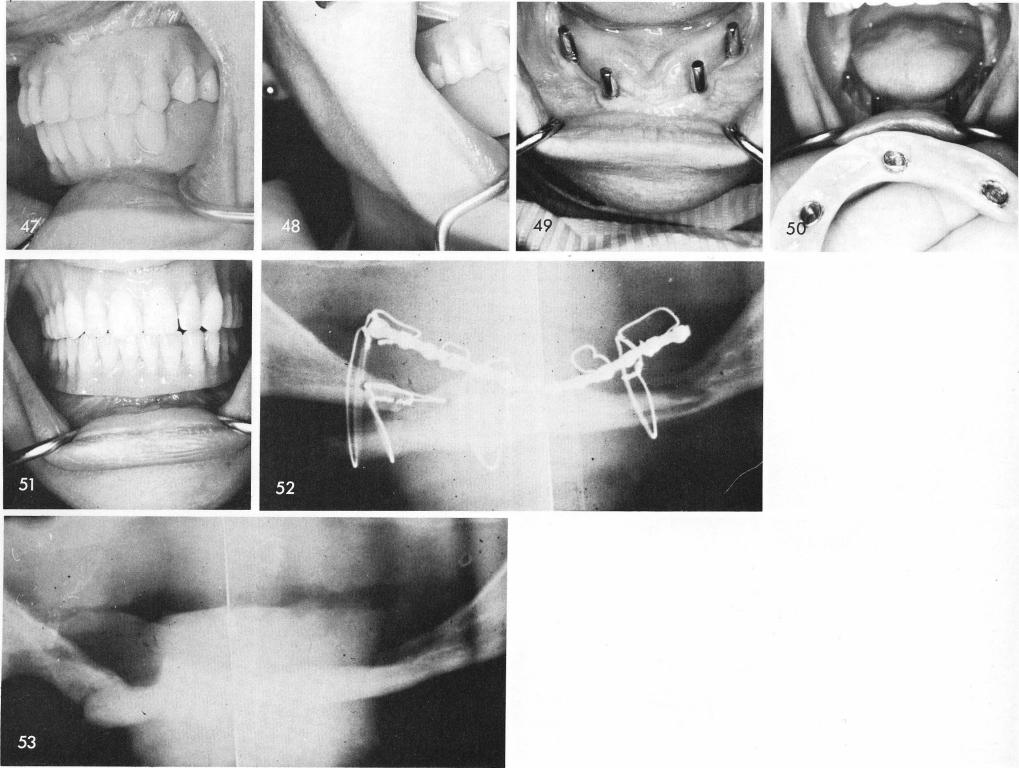

above the right mental bundle than the left one, figs. 39, 40, 41. The implant, usually fenestrated along most of the labial and buccal peripheral strut except for the areas that circumvent the mental bundles is inserted, figs. 42, 43, and the temporary acrylic stent which includes six anterior acrylic teeth and two geometrical planes of occlusion posteriorly is fitted over the implant posts, fig. 44. It should be quite a distance away from the bone and should occlude accurately to the existing upper denture as it was fabricated from a "bone bite". The tissues are sutured closed, fig. 45, and the acrylic stent is once more fitted, fig. 46, making certain of proper occlusion, figs. 47, 48, and being certain that its base is implant borne only.

The necks of the subperiosteal implant must always be in attached gingivae thus the posterior protruding posts should always be on or very near the mylohyoid ridges, fig. 49. The implant denture is snapped into position, figs. 50, 51.

This fractured mandible was wired to the patients existing all acrylic denture, which cannot be seen on an x-ray, fig. 52. At the end of eight weeks a complete bony union had been accomplished, fig. 53, although the body of the mandible on the right side was extremely foreshortened.

1 Necks of mandibular subperiosteal implant placed in attached gingivae